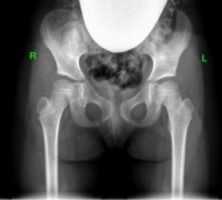

Слева: Рентген здорового бедра у взрослого. Стрелой отмечена суставная щель между крышей вертлужной впадины (Acetabulum) и головкой бедренной кости (Caput femoris). Справа: Рентген тазобедренного сустава, изменённого вследствие артроза, неравномерные высветления указывают на дегенеративные изменения. © Gelenk-Klinik